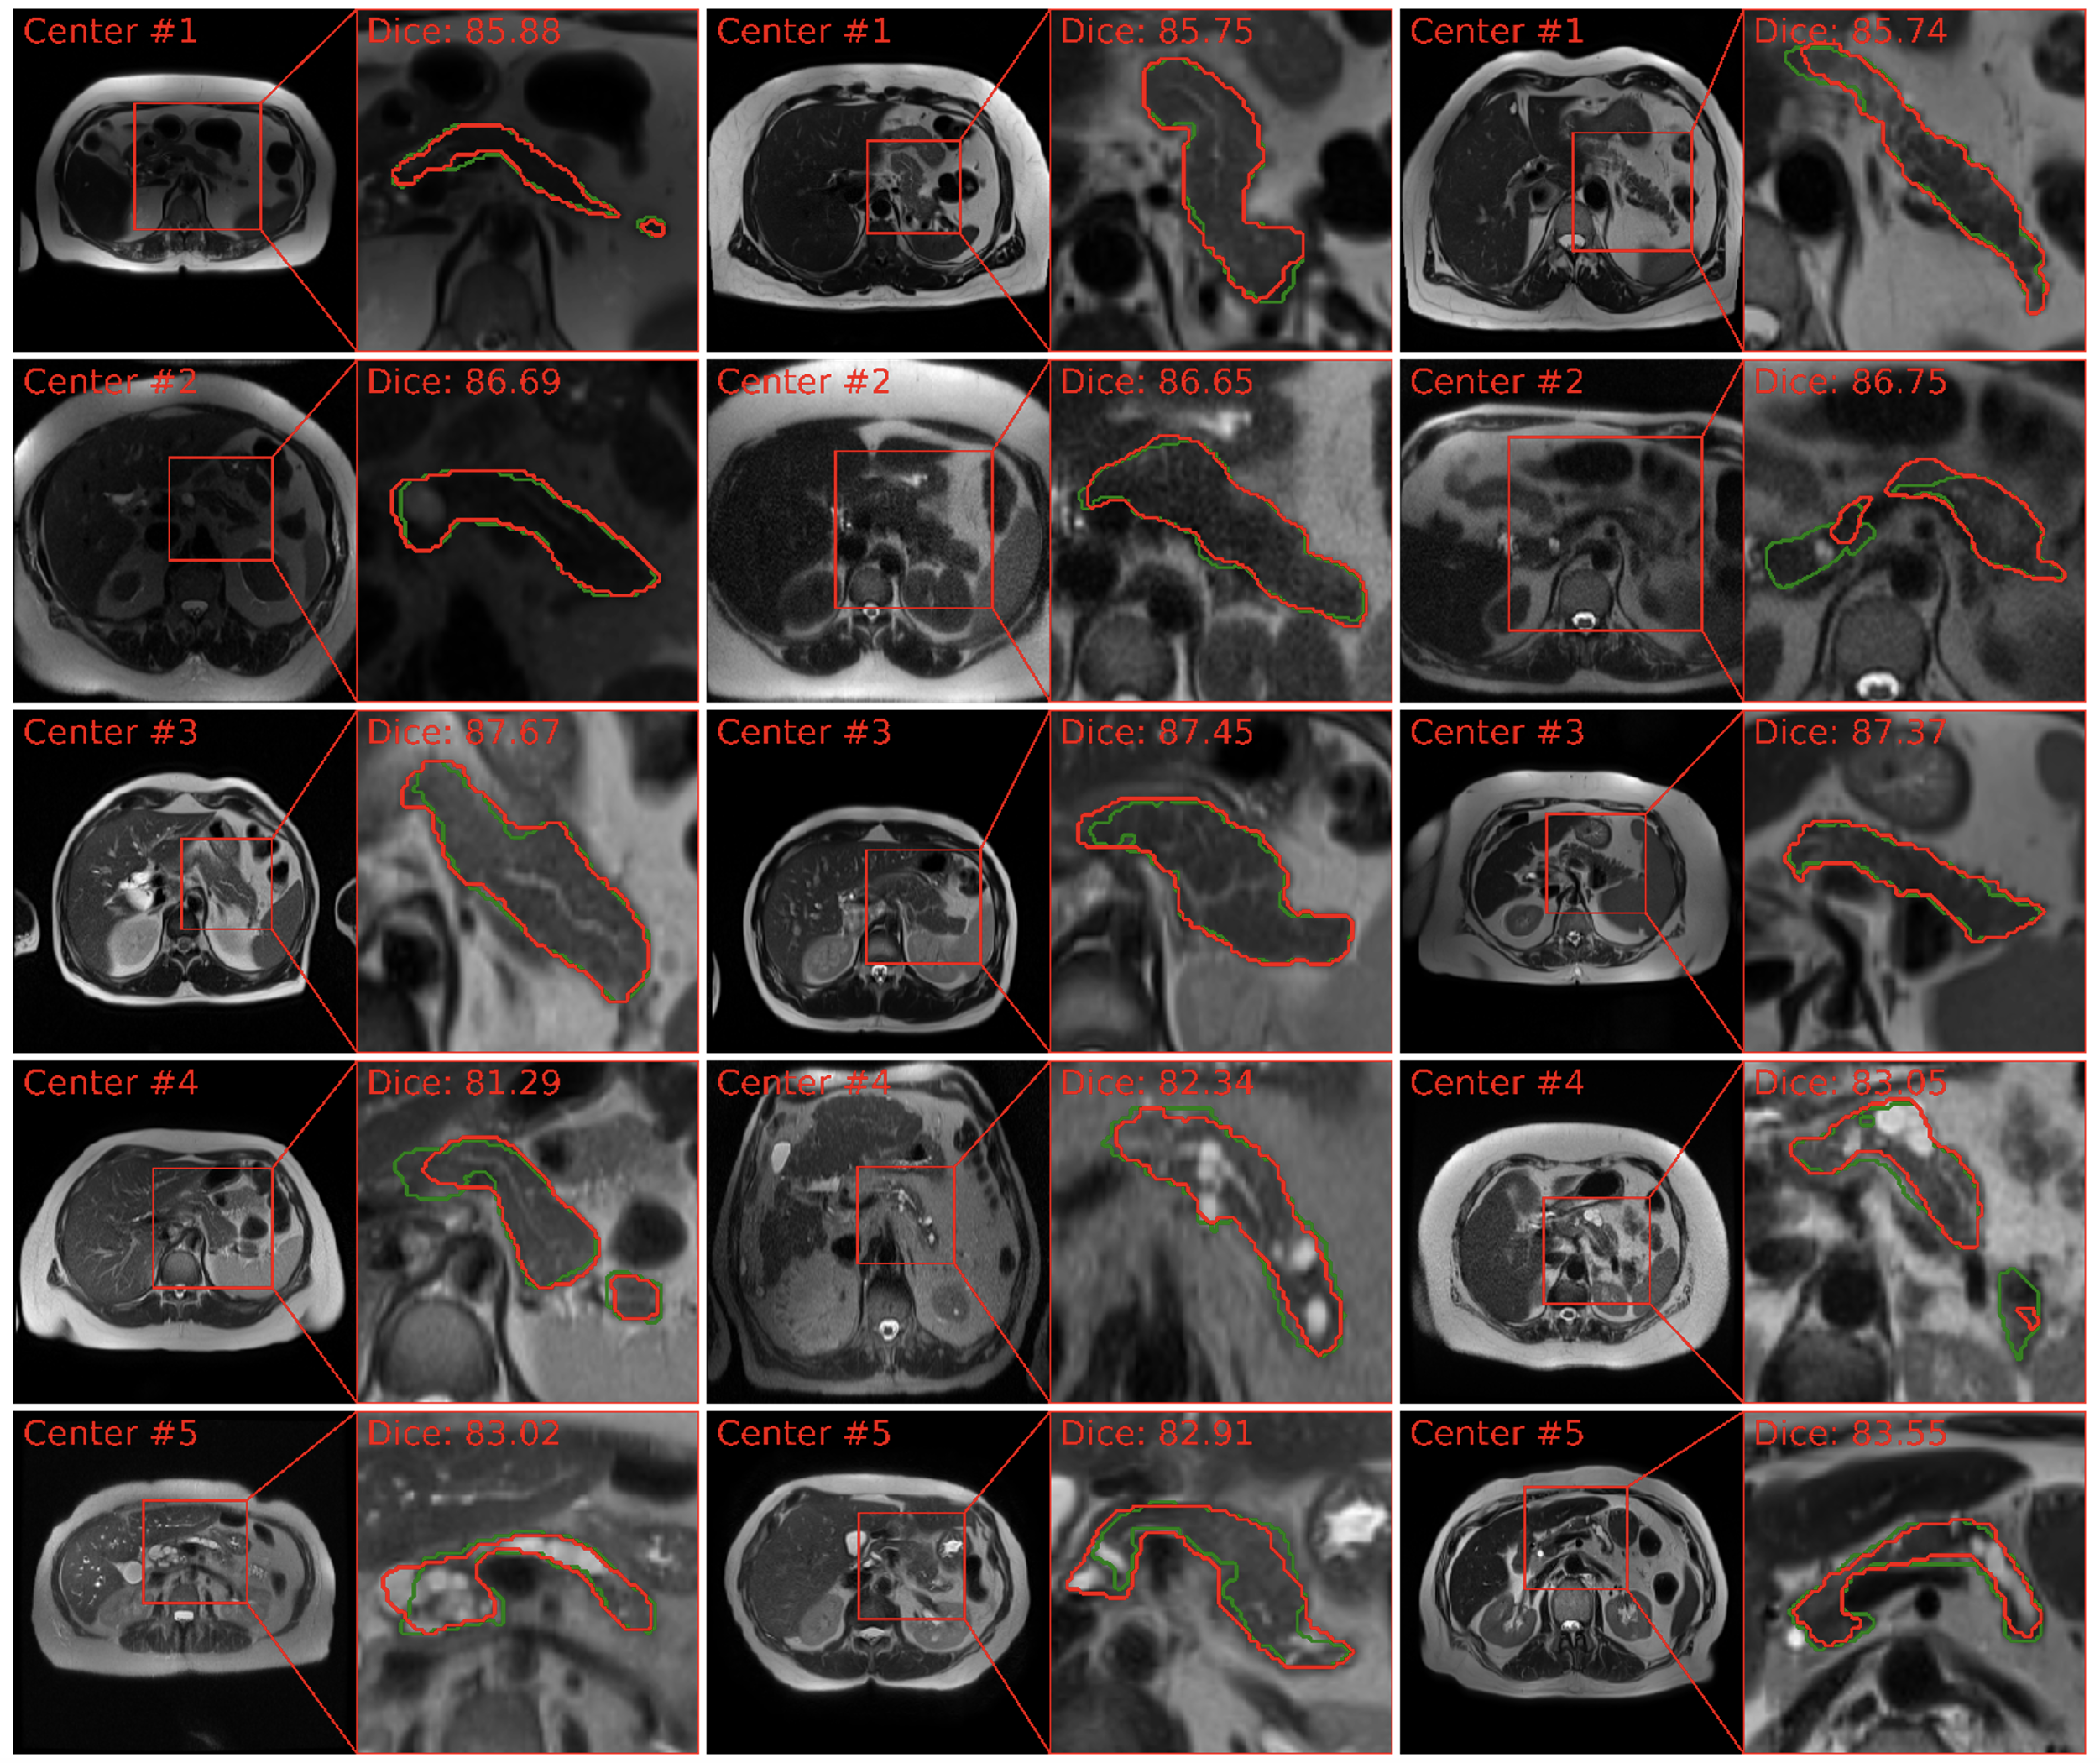

For T1W MRI segmentation, PanSegNet exhibited noteworthy performance within the source domain, achieving average Dice scores of 85.02% (±7.90%, median 87.26%) with HD95 distance of 6.37 mm (± 7.96, median 4.40 mm). Specifically, within the Center#1 and Center#2 datasets, our model achieved an average Dice coefficient of 86.44% (±7.04, median: 88.89%) and 83.70% (±8.41%, median: 86.01) (Table 4). Our results exhibit the model’s proficiency in accurately delineating pancreatic structures within the T1W modality. This strong segmentation capability was further visually validated through our segmentation results in Figure 5, which closely aligned with ground truth annotations.

Refer to caption

Fig. 5: MRI T1W pancreas segmentation visualization across various data centers. The segmentation delineations illustrate the model’s capability to delineate pancreas boundaries precisely, exemplified by the accurate results. We observe domain shifts in external validation from Centers #3, #4, and #5.

We also observed domain-shift in segmentation performance when conducted external validation. The Dice scores decreased to 81.55% (-4.08%, p-value: 1.92×10-2), 79.80% (-6.13%, p-value: 7.96×10-3), and 76.21% (-10.36%, p-value: 2.04×10-8), respectively, for data from three different centers. We also performed experiments with the publicly available AMOS dataset as it includes 40 MRI scans for pancreas, and the Dice score also dropped to 81.14% (-4.56%, p-value: 8.44×10-3). While these reductions highlight the challenges posed by domain shifts, it is worth noting that our model still maintained a strong performance even in these cross-domain scenarios.